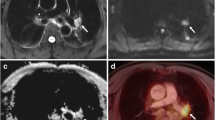

According to histopathology, T staging was correct with transverse T2 BLADE in 69 % of patients, with coronal HASTE in 67.9 %, with contrast-enhanced T1 FLASH in 59 %, with TrueFISP in 57.1 %, with non-enhanced T1 FLASH in 50 %, with transverse T1 3D Dixon VIBE in 45.2 % and with coronal T1 3D Dixon VIBE in 47.6 % (Figs. 1 and 2; Online resource 1). While the number of inaccurate evaluations of extrapulmonary spread were comparable among all sequences, inaccurate lesion detection and tumour site estimation were especially problematic with T1 FLASH and with coronal and axial T1 3D Dixon VIBE (Table 1).

Tumour diameter on transverse T2 BLADE correlated best with the actual tumour diameter and showed the smallest limits of agreement in Bland-Altman analysis. Tumour diameter on transverse and coronal T1 3D Dixon VIBE used for attenuation correction had the widest limits of agreement and showed a worse correlation than the diameters determined with the other MR sequences (Figs. 2 and 3, Table 2, Online resource 2).

An 84-year-old patient with squamous cell carcinoma in the right upper lobe: a–c PET/CT, d–j PET/MR. On histopathological work-up, the maximum tumour diameter was 33 mm. As no pleural invasion was present (d, e), pathological T stage was 2a. While correct T staging was possible with a maximum tumour diameter of 31 mm on T2 BLADE images (d, h) and 38 mm on T2 HASTE images (j), underestimation of the maximum tumour diameter on T1 3D Dixon VIBE images (g, i; 20 mm in axial orientation) led to downstaging with this MR sequence

The best detectability of the primary tumour against the surrounding background was found with transverse T2 BLADE (mean 2.55), transverse contrast-enhanced T1 FLASH (mean 2.46) and coronal HASTE (mean 2.67). Detectability was low particularly with non-enhanced T1 FLASH and 3D Dixon VIBE, (Figs. 2 and 4; see Online resources 3 and 4 for further information).

Alignment of the PET findings with the primary tumour worked best with transverse T2 BLADE while problems were observed with non-enhanced T1 FLASH and transverse T1 3D Dixon VIBE (Fig. 5; see Online resources 5 and 6 for further information).